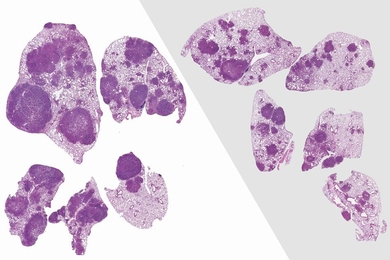

Two drugs that block cell division synergize to kill tumor cells.